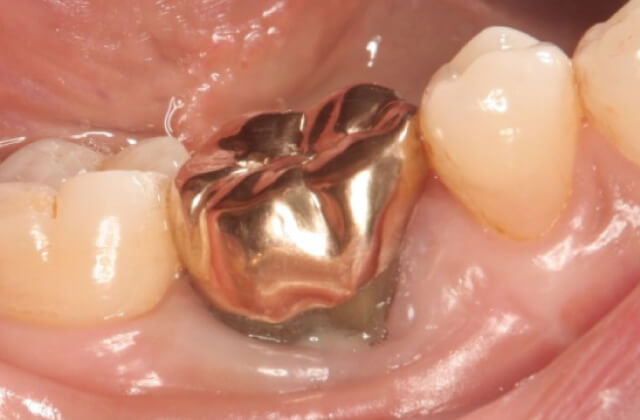

金歯による修復を希望されたので金による被覆をして終了しました。その後、硬い物だけは注意して食事していただいています